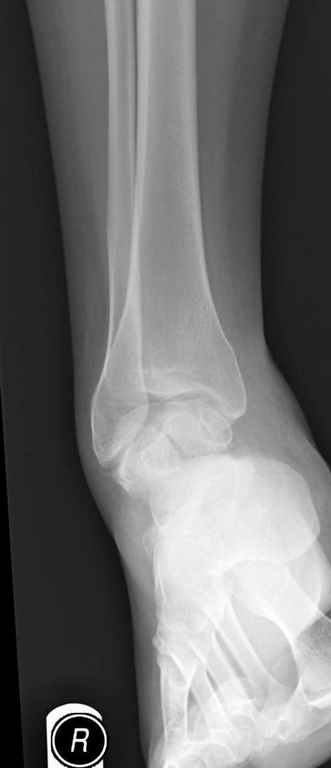

Вдогонку по поводу перелома таранной кости, больная 81, не страдает диабетом, перелом закрытый, в первый же день поступления ограничились временным наружным фиксатором (как на снимке).

Планировалась открытая фиксация после спадения отека, но больная пожелала лечиться по месту жительству в другом штате..

Примеры на снимке...